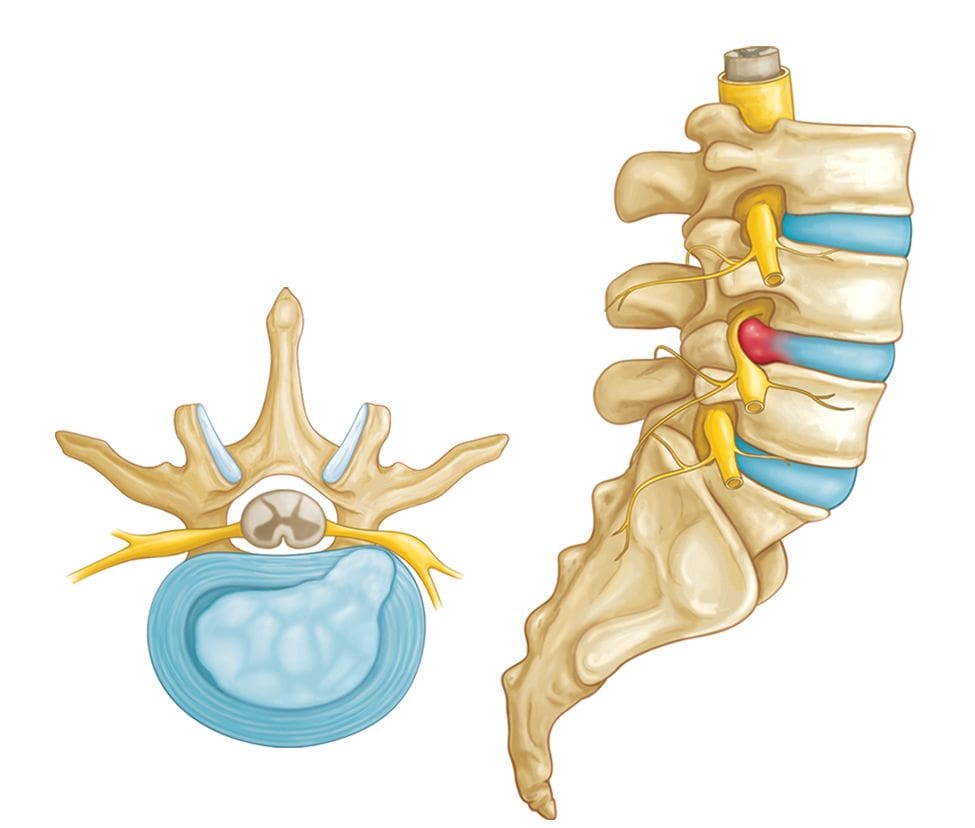

КТ-протрузии дисков: Визуализация и классификация